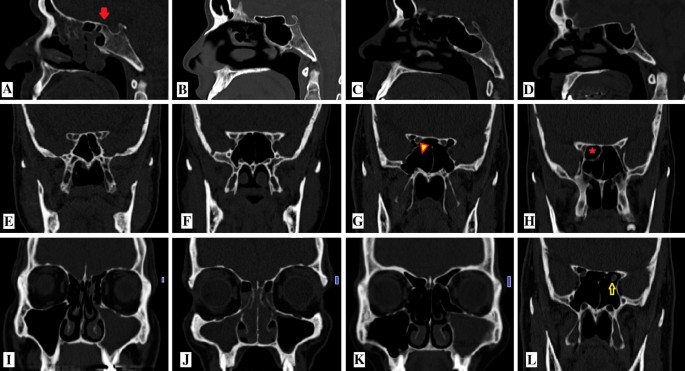

Pdf Analysis Of Pneumatization And Neurovascular Structures Of The Sphenoid Sinus Using Cone Beam Tomography Cbt

Http Rjr Ro Files Library 05 20rjr 2004 20ct 20study 20of 20the 20sphenoid 20sinus 20pneumatization 20types Pdf

Giant Pneumatization Of Sphenoid Sinus Report Of Four Cases And Review Of Literature

A Presellar Type Of Sphenoid Sinus B Postsellar Sphenoid Sinus In Download Scientific Diagram

Assessment Of Variations In Sphenoid Sinus Pneumatization In Indian Population A Multidetector Computed Tomography Study Semantic Scholar

Cone Beam Computed Tomography Analysis Of Sphenoid Sinus Pneumatization And Relationship With Neurovascular Structures Springerlink

The Impact Of Sphenoid Sinus Pneumatization Type On The Protrusion And Dehiscence Of The Adjacent Neurovascular Structures A Prospective Mdct Imaging Study Academic Radiology